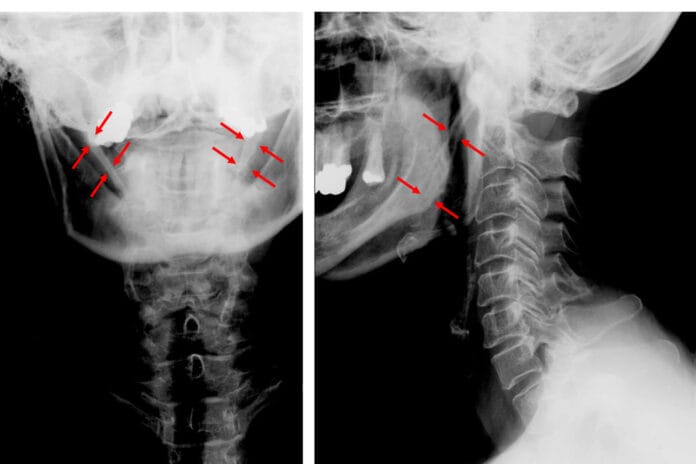

Eagle Syndrome: Dental Professionals can Identify Painful Condition on Panoramic Radiograph

Eagle syndrome (stylohyoid syndrome) is within the category of many other conditions since there are no definite known causes. Pain is experienced in the...